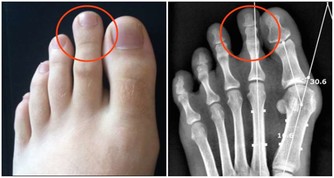

2. 膕窩穴位:委中穴

常按摩此處,對治坐骨神經痛有效果

提醒:膕窩囊腫患者不適合按摩該部位

膕窩是膝後區的菱形凹槽,裡面的血管和神經非常豐富,

經常拍打有行氣活血、緩解痙攣的功效。

膕窩處一個很重要的穴位叫委中穴,經常按摩,

對常見的坐骨神經痛、小腿疲勞、脖子痠痛、臀部疼痛等疼痛性疾病有良好作用。

南京市中西醫結合醫院骨科副主任醫師王睿說,

委中穴在膕窩正中,為人體足太陽膀胱經上的重要穴道之一,

主治疾病為:坐骨神經痛、小腿疲勞、肚子疼痛等。

但有一種情況是不適合按摩和刺激這個部位的。

那就是膕窩囊腫的患者,膕窩囊腫泛指膕窩內的滑囊炎,

是因為膝關節積液,屈膝時腔內壓力增高,迫使滑液後移形成的一種疾病,

如果給予按摩刺激,不但不利於健康還會延誤治療。